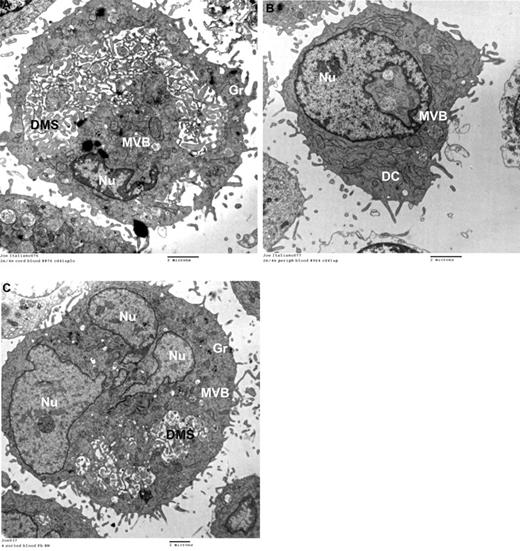

To confirm that the lower CD42b levels indeed reflected less-mature MKs, we also evaluated the ultrastructure of rapamycin-treated CB-MKs by electron microscopy. In this study, 81% of control MKs (DMSO-treated; n = 90) exhibited a DMS (Figure 7A), compared with 41% of rapamycin-treated MKs (n = 85). Most rapamycin-treated MKs exhibited scant cytoplasm, few granules, and an absent DMS (Figure 7B).

Ultrastructure and protein-expression levels of GATA-1 and C-MPL in rapamycin-treated versus control CB-MKs. (A) Representative electron photomicrograph of a CB-MK cultured in 0.01% DMSO (controls) exhibiting a large cytoplasm, a large cytoplasm/nucleus (Nu) ratio, abundant granules (Gr), and an open DMS. (B) Ultrastructural characteristics of MKs treated with rapamycin showing a striking reduction in cytoplasm, nearly absent granules, and a lack of DMS. Features of very immature MKs were frequently observed, including multivesicular bodies (MVB) and dense compartments (DC). (C) Under the same experimental setting described in Figure 4, MKs were starved overnight and then stimulated with TPO in the presence or absence of rapamycin (50nM). Pretreatment with rapamycin significantly suppressed phosphorylation of S6K and 4E-BP-1 upon TPO stimulation in CB-MKs. (D) In separate experiments, MKs treated with rapamycin from day 11 until day 14 of culture had significantly lower protein levels of GATA-1 and C-MPL compared with control MKs. Bars reflect the means ± SEM of 3 independent experiments. *P < .05.